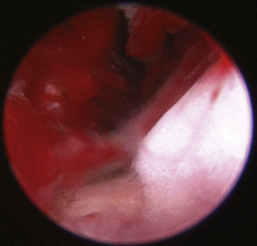

Rhinoscopic sequence imaging of TNC debridement of a feline caudal nasal and nasopharyngeal adenocarcinoma is depicted in Figures 19-63 through 19-69.

image

Figure 19-63 Transnares curettage sequence: feline nasal adenocarcinoma of the right caudal nasal cavity and nasopharynx, evaluation of the tumor extent, tumor debridement, and reevaluation of lumen patency after the procedure.

Figure 19-65 Full mass obstruction is present, filling the nasopharynx and preventing air flow bilaterally.